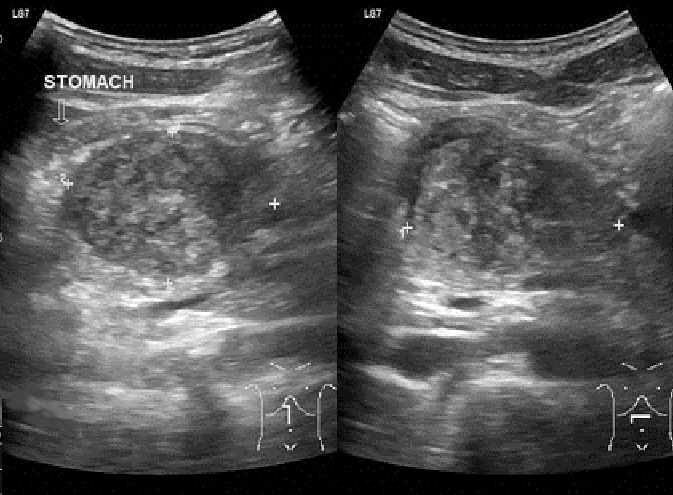

Signe

direct frequemment d'une traumatisme du pancreas est

aspect enlargement volumineuse a hypoechogene , non

homogene du pancreas . Image echographique au

dessus est image echo- percutane de l'abdomen en

coupe verticale et transversale epigastrique a

travers le pancreas . |

|

Aspect enlargement a

hypoechogenecite , non homogene du corps d'une

traumatisme du pancreas , la lesion est volumineuse

a longitudinal du corps pancreas , epanchement

liquidienne peripancreatique peut en s'obsreve sur

la coupe transverse . Image echographique

percutane de l'abdomen .a travers le pancreas |